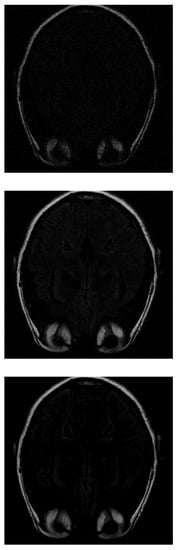

As in IRLS, the ISTA algorithm first detects the areas of highest intensity in the first measurements without distinguishing the white matter (Figure 6 top). If the number of input data is increased, the border resolution increases, but it is still difficult to differentiate the white matter (Figure 6 middile). Finally, the resolution increases until the shape of the fat is detected (Figure 6 bottom).

Figure 6. Reconstruction of the image in Figure 3 using ISTA with 30 % (top), 70 % (middle) and 100 % (bottom) of taken measurements.

Mathematics 11 03573 g006